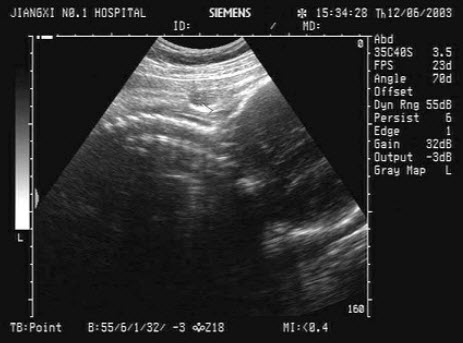

男,49岁,上腹不适1个月余。结合超声声像图,诊断为()

A.肝血管瘤

B.肝癌

C.局限性脂肪肝

D.肝脓肿

E.肝囊肿